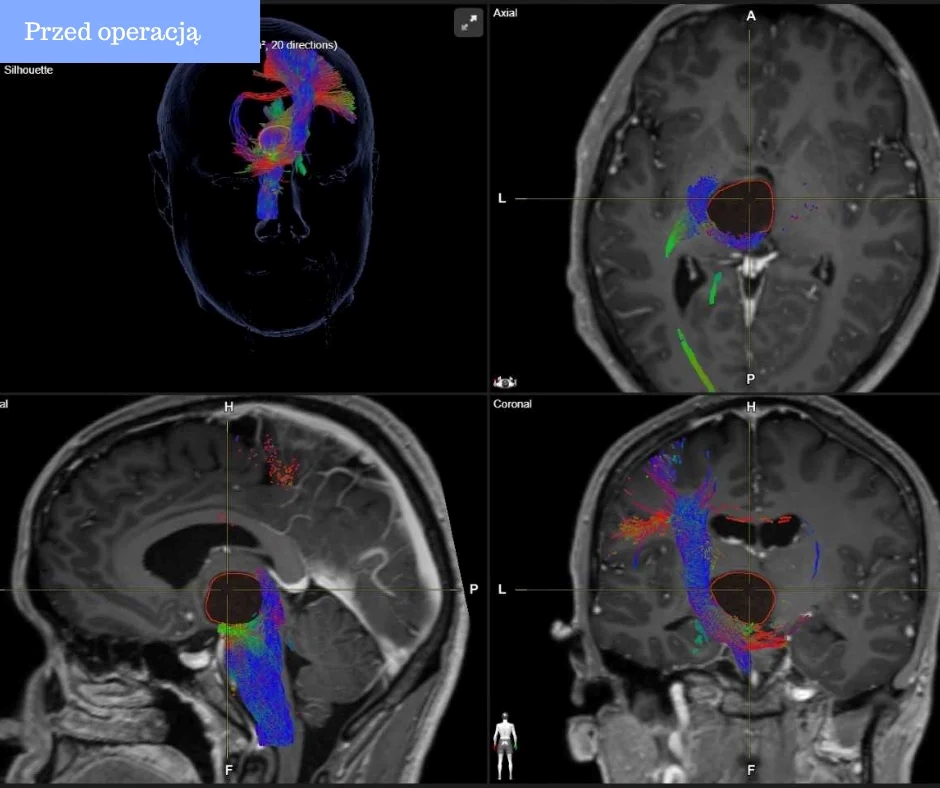

🔬 У рамках проєкту NeuroExcellence/Нейродосконалість без кордонів лікарню було оснащено високоточною системою нейронавігації. Це інноваційне обладнання дозволяє нейрохірургам працювати з максимальною точністю, мінімізуючи ризики для пацієнта, уникати складних та травматичних втручань і значно скорочувати період відновлення.

Саме нейронавігація стала вирішальним фактором під час надзвичайно складної операції, коли лікарі змогли провести мінімально інвазивне втручання замість небезпечної трепанації черепа. Завдяки точному доступу через голку всього 2 мм операція пройшла успішно.